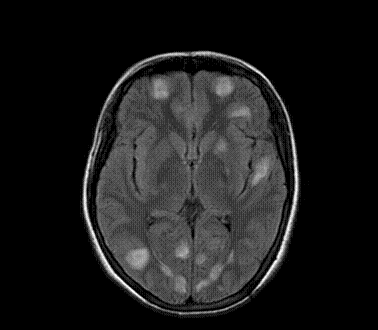

以下是引用xly在2009-5-20 11:38:00的发言:[br]大脑、小脑及脑干多发结节状及环状稍长t1、长t2异常信号影,部份病灶中心见稍短t1、短t2信号,病灶边缘光滑、边界清楚,灶周环状水肿,dwi为低信号,增强扫描上述病灶均匀强化,部份病灶中心无强化,脑膜小结节异常强化,考虑脑膜脑结核可能性大。胸片如何?ppd如何?期待结果。